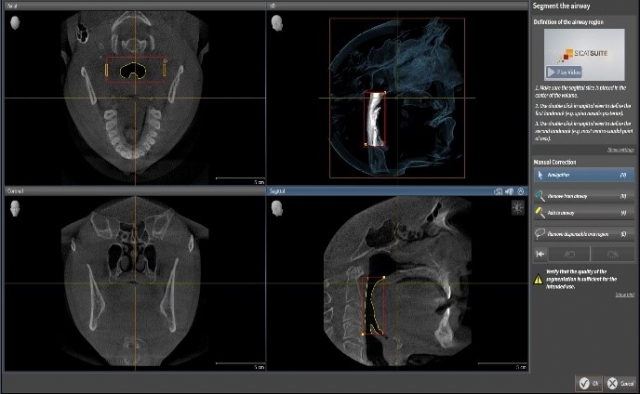

If you are planning on using software like SicatAir to compare airway volume at that position compared to maximum intercuspation, then it might be a good idea to leave the silicone, and you could even take out the lower part of the bite fork, allowing the patient to bite solidly into the material (Figs. 9–12).

That entire digital file can then be uploaded and sent to fabricate an appliance, capturing the position of the mandible, while confirming the anticipated volume (yes, I know the patient is awake and sitting up. If you find a way to take a scan with the patient supine and asleep, it would be even better, right?) (Fig. 13)